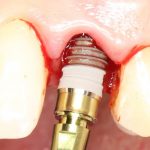

Рекомендации по установке имплантов. Для всех. Часть III